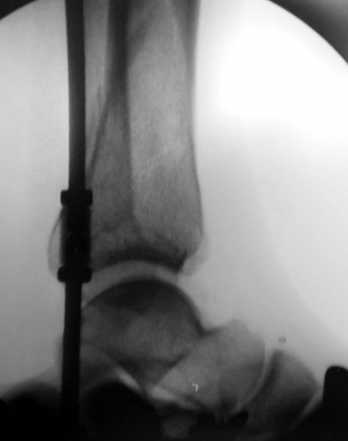

Пример - довольно похожий перелом, оперированный в первые 8 часов после аварии у 40-летнего больного, страдающего тяжёлым сахарным диабетом 1 типа.

По поводу обсуждаемого случая - 6-недельная фиксация такого перелома значительно увеличила шансы на артроз голеностопного сустава. Дальнейшая фиксация в гипсе практически сравняет эти шансы со 100%.

Мне кажется, что есть два возможныых варианта дальнейшего ведения:

1- открытая редукция с наложением аппарата Илизарова и разработка движений в суставе.

2.- снятие гипса, разработка сустава, И коррегирующая супрамаллеолярная остеотомия с фиксацией в аппарате Идизарова через полгода.